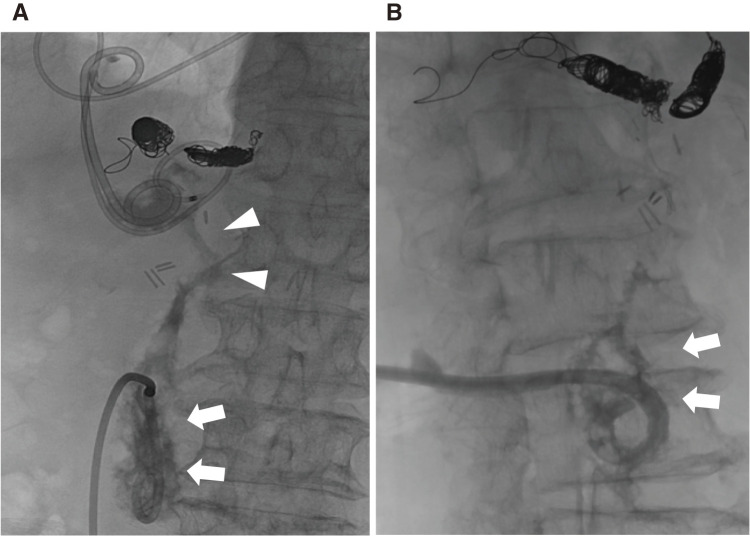

一名 60 多岁的男子因腹主动脉瘤破裂接受了开腹移植物置换术,术后出现了胰腺假性囊肿。患者接受了内窥镜引流术,但由于移植物周围空腔大面积沟通,导致主动脉移植物感染。为了同时处理胰瘘和移植物感染,患者接受了经皮引流术。虽然胰腺假性囊肿缩小了,但主动脉移植物感染仍然存在。随后,进行了主动脉移植物部分置换术,并用大网膜瓣覆盖。他口服抗生素后出院,10 个月后感染没有复发。

A man in his 60s developed a pancreatic pseudocyst postoperatively after an open graft replacement for a ruptured abdominal aortic aneurysm. Endoscopic drainage was performed; however, this led to an aortic graft infection due to macroscopic communication with the perigraft cavity. Percutaneous drainage was performed to manage the pancreatic fistula and graft infection simultaneously. Although the pancreatic pseudocyst diminished, the aortic graft infection persisted. Subsequently, partial aortic graft replacement with greater omental flap coverage was performed. He was discharged with oral antibiotics, with no recurrence of infections at 10 months.